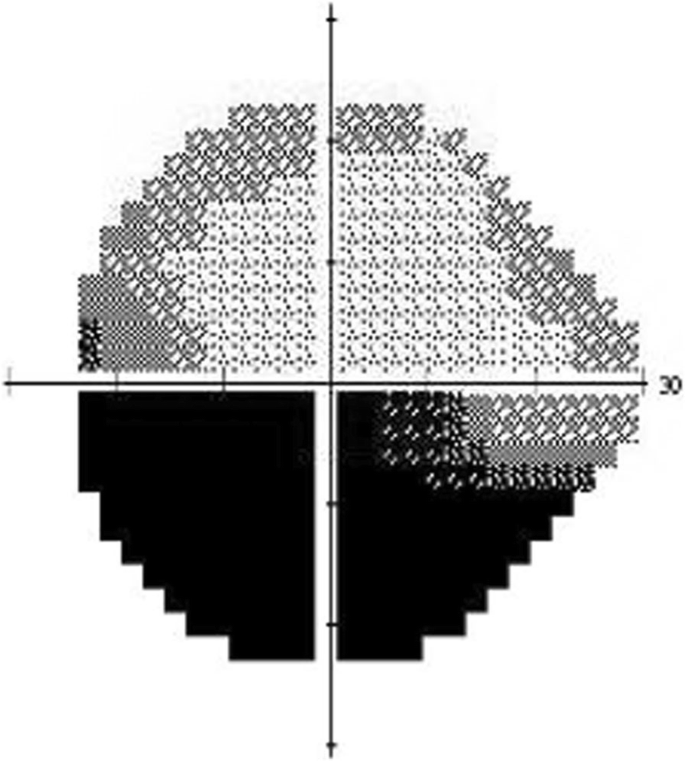

Non-arteritic anterior ischemic optic neuropathy (NAION) is the most common cause of acute optic neuropathy in patients over age 50 years, and many affected individuals suffer from permanent visual deficits. [1] The primary mechanism for NAION is thought to be acute hypoperfusion of the optic nerve from the posterior ciliary artery branches. [2] Systemic risk factors for the development of NAION include diabetes, systemic hypertension, nocturnal hypotension, blood loss, obstructive sleep apnea, and hypercoagulable disorders. [3,4,5,6,7,8,9] Presenting features include painless monocular visual loss, a relative afferent pupillary defect in the involved eye, and optic disc edema, often with peripapillary hemorrhages. Visual field testing commonly shows altitudinal defects, although other patterns of visual field loss can occur (Fig. 1). After resolution of edema, disc pallor, often in a segmental pattern, typically results. Although steroid treatment in the acute phase has been recommend by some experts, [2] no treatment has proved effective for this condition.

Participants underwent routine clinical testing at their initial appointments, including visual acuity testing, fundus photographs, optical coherence tomography (OCT) of the ganglion cell layer-inner plexiform layer and retinal nerve fiber layer using the Zeiss Cirrus OCT (Carl Zeiss Meditech, Inc.), and Humphrey visual fields (30–2 Swedish Interactive Thresholding Algorithm standard program). All testing was performed in both the affected and unaffected eyes. Additionally, on the initial imaging day, imaging was performed with the RFI. Each subject in this study was treated at the discretion of her/his neuro-ophthalmologist and not according to a treatment protocol. Some patients were offered steroid treatment, after discussion regarding lack of evidence for benefit, if they had no comorbidities (e.g., poorly-controlled diabetes mellitus) that precluded steroid use. Any treatment was documented at the initial appointment and throughout the follow up period. Similar testing, including RFI, was performed initially within 2 weeks of symptom onset, then again at 1 month and 3 months after the onset of vision loss. Two patients withdrew after the 1-month imaging session, and 3 patients completed the planned imaging sessions.